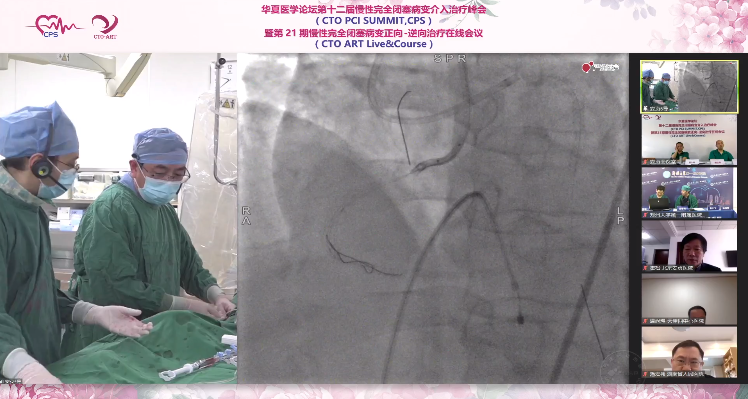

3.尝试1.25mm球囊通过RCA中段闭塞病变未成功,球囊扩张后仍无法通过,送双腔微导管至RCA第二转折,使用Conquest Pro 8-20导丝尝试寻找新路径通过闭塞病变,最终Knuckle通过第二转折,观察导丝位于支架内。

4.撤出双腔微导管更换Corsair微导管,并可送至第二转折之后,反复尝试后CP 8-20导丝可至RCA远端,但影像提示位于远段支架上缘,不能完全确认导丝远端位于原支架内,反复尝试后CP 8-20导丝仍不能至后侧支。